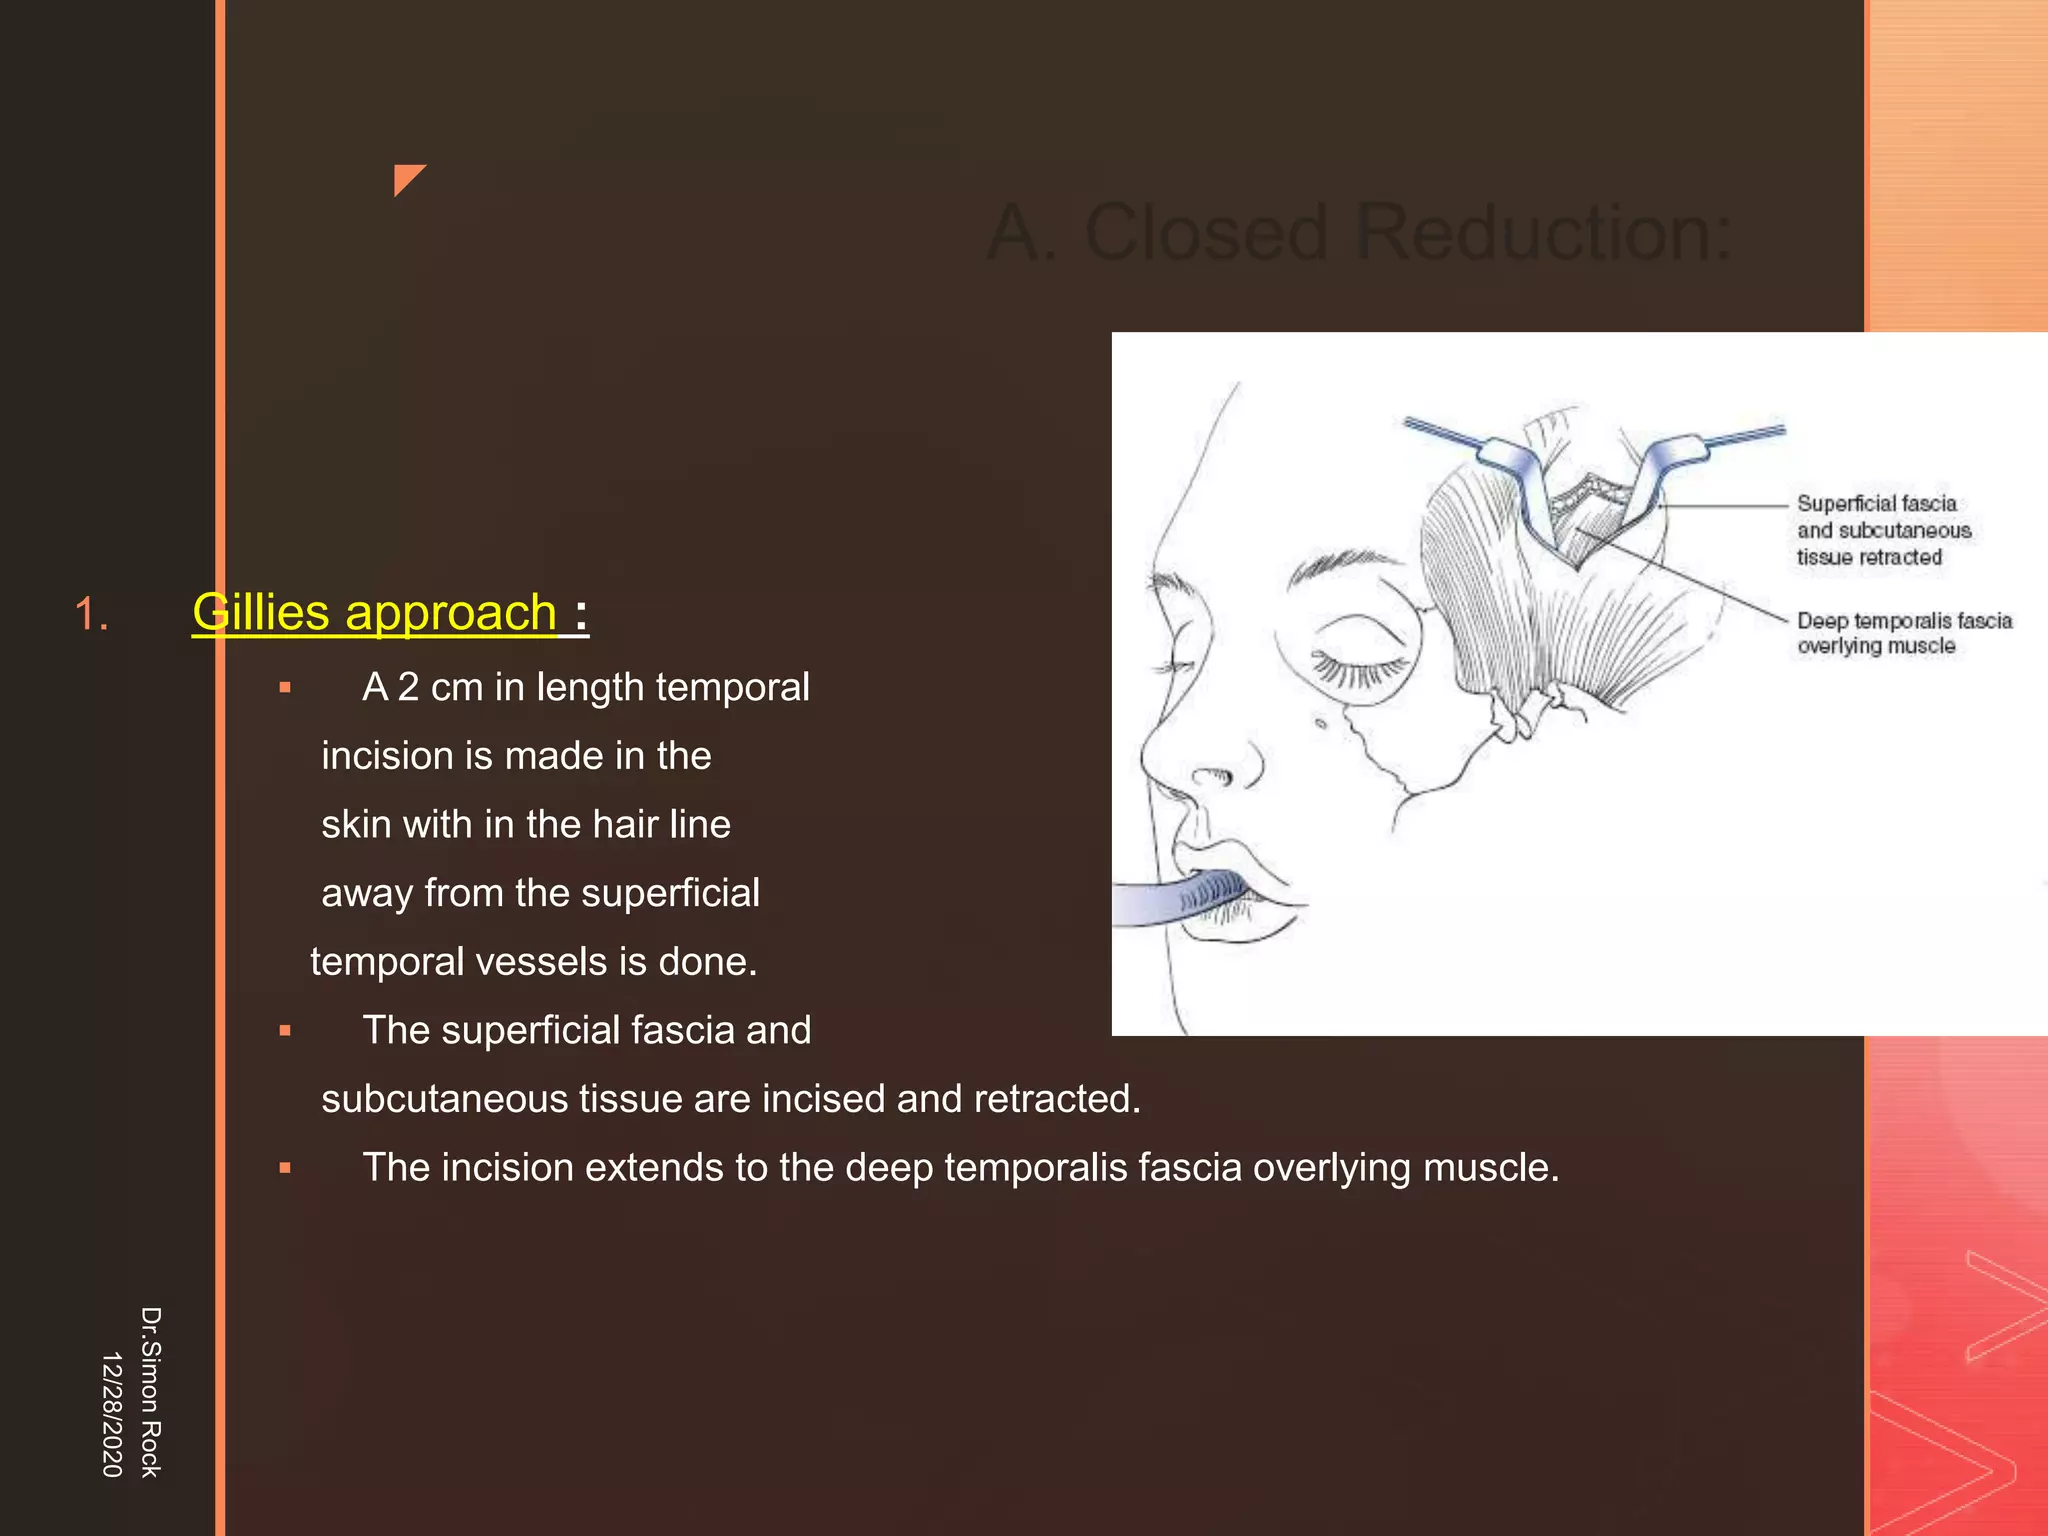

This document discusses the anatomy and fractures of the zygomatic bone. It notes that the zygoma forms the cheekbone and articulates with several other facial bones. Zygomatic fractures most commonly occur in the arch or body due to blunt trauma. Diagnosis involves checking for diplopia, ecchymosis, and other signs of orbital or facial bone involvement. Treatment may involve closed or open reduction based on the severity of displacement. Closed reduction techniques try to elevate the bone back into position without surgery, while open reduction requires surgical exposure and fixation of the fracture site.